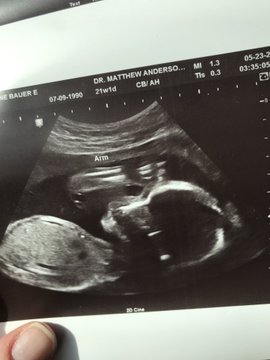

To combat the dehumanization that helps many like Raimondo feel comfortable with taking away the lives of preborn babies, Nichole combined the powerful tools of social media and ultrasound imaging: “We combat the lie of dehumanization by showing a side-by-side photo of the child in the womb (Me) and outside the womb (…Still Me), clearly presenting the continuum of human life from the womb to the crib.”

Nichole sent the card back to the governor, along with her #MeStillMe images of her oldest son and newest baby. She later created a Facebook page and a Twitter account to spread the hashtag. Pro-lifers from about half a dozen other states have shared the hashtag, and two pro-life Catholic media outlets, EWTN and Relevant Radio, have shared with millions of followers. Many have taken up the hashtag to share photos of their own babies, both born and preborn.